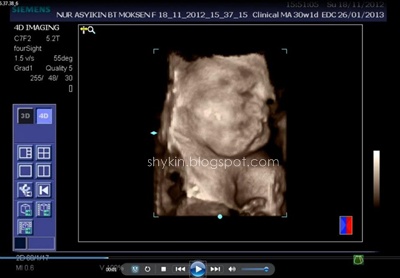

Dulu masa pregnant Fayyadh dan Fathi scan 2D je yang aku tahu. So, Kali ni konon-konon nak merasa la scan 3D. 4D pulak, aku pun ajak la suami pergi buat dekat klinik. Memang teruja la sebab 4D bole dengar sound dan tengok dia gerak-gerak dengan gambar coklat tu. Dah macam ada kat depan mata je baby padahal masih lagi dalam perut. Jakun jugak la haku... ngeh ngeh ngeh.

BTW aku buat dekat Klinik Sofea, Puchong Utama, scan 3d 4d murah la kat situ, RM80 sekali dengan CD. Setakat ini aku rasa kat KL ni tu yang paling murah. Lagi pula, tak payah buat appointment, walk-in terus je.

Proses scan dijalan oleh doktor yang bertugas masa tu. Okeyla jugak, puas hati sebab dia print hampir 10 keping result scan muka tu. Banyakkan??..

Jom view hasil 4dscannya. Yang ni aku printscreen dari VCD yang klinik tu bagi.

Nyenyak tidur, usik-usik pun tak bangun.